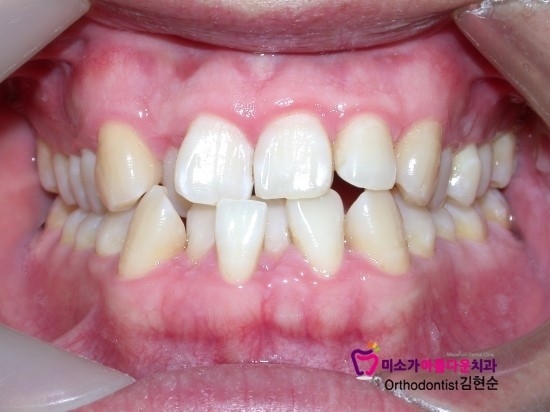

학동역치아교정잘하는치과 미소가아름다운치과 덧니교정 과정

입안에 덧니가 상당히 많아서 발치 후 교정을 한 사례입니다.

덧니가 이 정도로 심하고 입안에 치아를 배열시킬 공간이 없을 경우

발치를 하는 편이 치열을 확실하게 고르게 해줄 수 있어서

발치 4개 후 교정기 제거하고 유지장치 부착한 사진입니다.